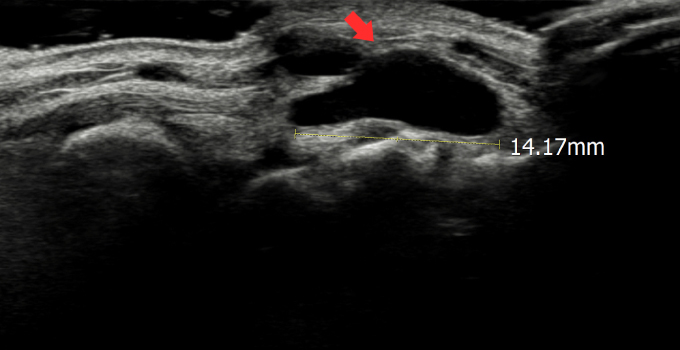

결절종

수부에 발생하는 가장 흔한 종양으로 손목의 관절을 둘러싸고 있는 얇은 성유성 피막 안에 투명하고 끈적이는 액체를 함유하고 있는 물혹성 종양입니다.

결절종 초음파 영상 사진